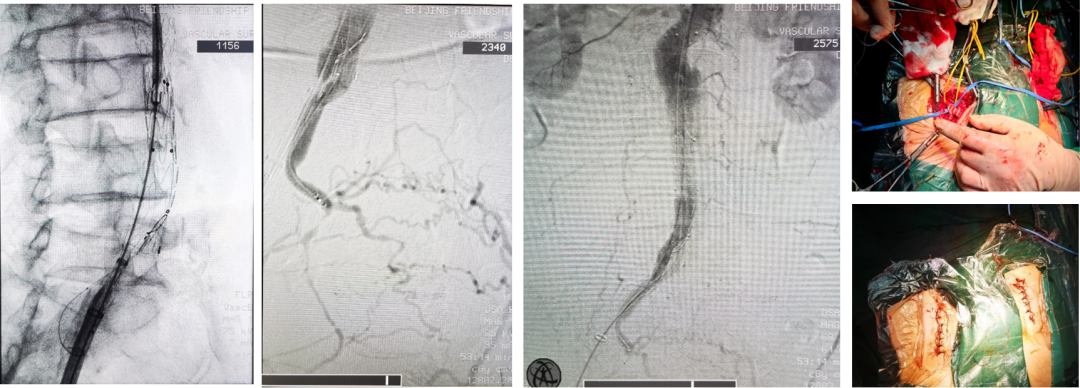

病例1:支架闭塞再干预

病情:患者男,70岁,8年前因腹主动脉瘤+双侧髂动脉瘤行EVAR术,左侧髂内动脉栓塞,右侧髂内动脉早期IBD重建。

难点:术后8年复查发现右侧髂支哆开、右侧髂支覆膜支架闭塞,髂内动脉瘤样扩张。原支架遮挡髂内动脉开口,残余操作空间不足1cm,传统方法难以再通。

手术策略

近端锚定重建:右侧髂支内植入美敦力髂支支架,建立G-iliac™近端锚定段。

导丝技术:导丝经髂支外侧间隙进入右侧髂内动脉壁支远端,避开闭塞段。

精准栓塞与重建:栓塞髂内动脉脏支,避免侧支出血;植入SilverFlow™覆膜支架至壁支远端,平行于原闭塞支架完成重建。

术后随访

术后19个月CTA显示:右侧髂内动脉壁支支架通畅,无狭窄或闭塞,瘤腔血栓化良好。